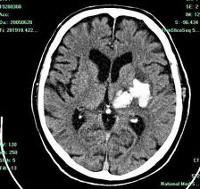

• КТ головного мозга. На томограммах внутримозговая гематома выглядит как очаг гомогенной плотности округлой или овальной формы. Если гематома возникла из-за ушиба головного мозга, она обычно имеет неровные контуры. Со временем плотность гематомы уменьшается до изоплотного состояния, соответствующего плотности мозговой ткани. Для малых гематом этот процесс занимает 2-3 недели, для средних — до 5 недель.

• МРТ головного мозга. При снижении плотности гематома лучше визуализируется с помощью МРТ. Однако на ранних стадиях МРТ может привести к ошибочному диагнозу, принимая гематому за опухоль с кровоизлиянием. Поэтому многие неврологи и нейрохирурги предпочитают использовать оба метода (КТ и МРТ) для диагностики.